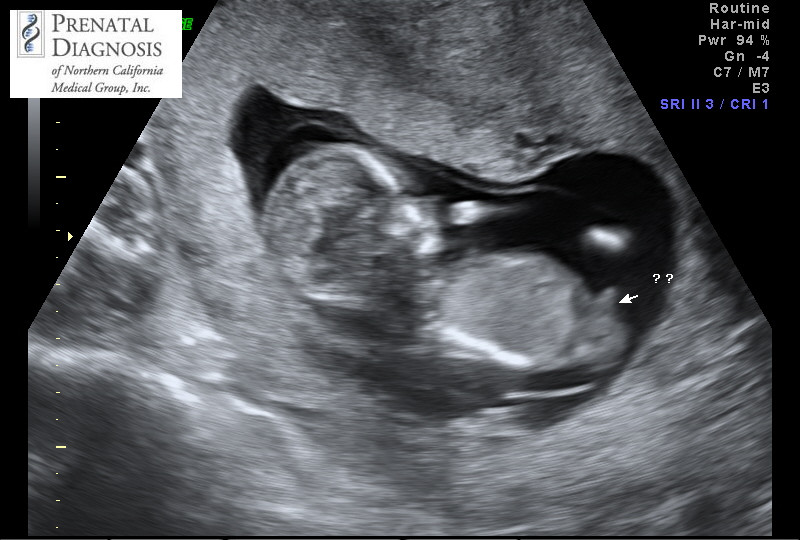

How accurate is nub theory? Other's experiences please! I am so anxious for mine to be right!

I posted a nub shot a week or so ago and everyone thought boy and after doing a ton of research so did I. Since, I have been on all kinds of forums and chats with so many conflicting views. One study on angle of the dangle looks so accurate and then I go onto babycenter and SO many people have boy fetus guesses at 13 weeks only to find out girl. Super curious on other's opinions and own experience. I have an elective scan coming up but will be 14 weeks and wondering if it's even worth it (they say they are 100% accurate for 25 yrs but who knows).